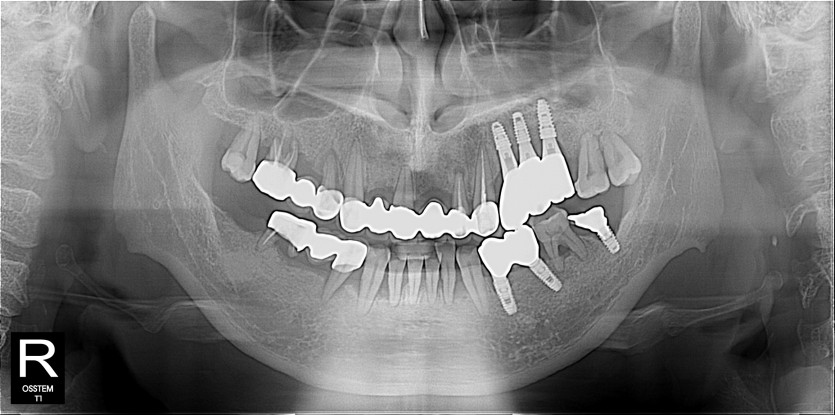

임플란트 사례